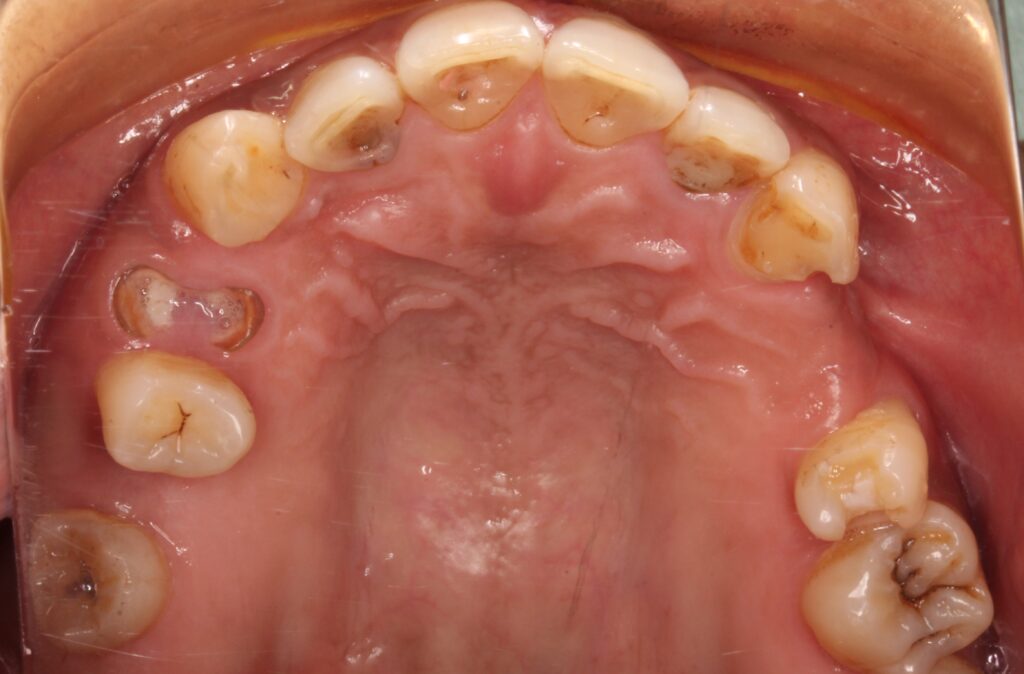

●寿命が長い

インプラントの寿命は大変長いです。

もし、しっかりと適切なメンテナンスを受け続ければ、インプラントは長期に保つことができます。

写真は記録の残っている方で最古参のもの。2004年に埋入し、今でも健全に機能しています。